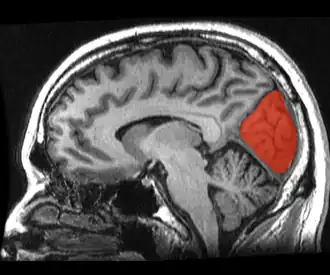

![]() Sagittal MRI slice with the cuneus and lingual gyrus shown in red. | |

The cuneus (from Latin 'wedge'; pl.: cunei) is a smaller lobe in the occipital lobe of the brain. The cuneus is bounded anteriorly by the parieto-occipital sulcus and inferiorly by the calcarine sulcus.

The cuneus (Brodmann area 17) receives visual information from the same-sided superior quadrantic retina (corresponding to contralateral inferior visual field). It is most known for its involvement in basic visual processing. Pyramidal cells in the visual cortex (or striate cortex) of the cuneus, project to extrastriate cortices (BA 18,19). The mid-level visual processing that occurs in the extrastriate projection fields of the cuneus are modulated by extraretinal effects, like attention, working memory, and reward expectation.